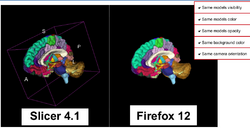

WebGL Export

- WebdGLExport

- Authors: Nicolas Rannou, Daniel Haehn, Children's Hospital

- This Slicer 4.1 webinar presents the new features and improvements of the release, and a brief overview of work for the next release.

- Authors: Steve Pieper Ph.D.

- Audience: First time users and developers interested in Slicer 4.1 new features.

- Length: 0h20m